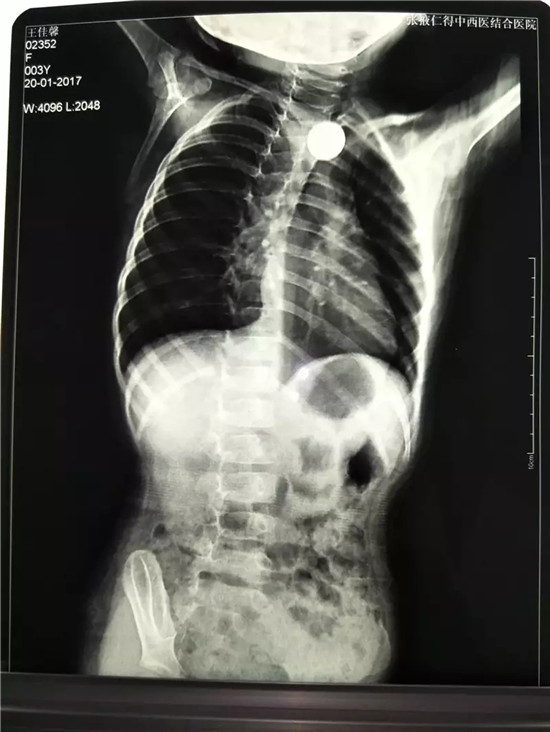

胸片显示:食道上段可见一异物

硬币卡在食道入口下方约1.5cm处

1月20日16:00,一名3岁小孩在家属的匆忙脚步声中来到河西学院附属张掖人民医院内镜中心。在医生的详细询问下,最终确定,小孩是误食硬币导致的消化道堵塞。由于小孩还不足3岁,消化道尚在发育中,因此硬币就卡在了她的食管内。初诊医院胸片显示:食道上段可见一异物,考虑到孩子年龄太小,不敢进行处理,才转入河西学院附属张掖人民医院进行治疗。

内镜中心护士长王彩虹遂上报医务科、消化科及麻醉科,积极协调相关人员。于16:30分,内科主治医师曹金滩、麻醉科副主任脱立雄在内镜室护士长王彩虹及主管护师张宏梅、彭云等的配合下,在静脉麻醉下行内镜下异物取出术。进镜顺利,硬币卡在食道入口下方约1.5cm处,遂用鳄嘴异物钳牢牢夹紧硬币,通过管道小心翼翼地把硬币取了出来,前后仅用10分钟就解决了问题,通过胃镜观察小孩的食管壁,没有发现损伤、出血,在场的医护人员都松了口气,孩子从入院到出院还不到一个半小时。 通过内镜下微创治疗,既避免了开胸手术带来的创伤,解除了患者的痛苦,又节约了费用。该例微创手术的成功体现了我院内镜治疗水平又上了一个新的台阶。